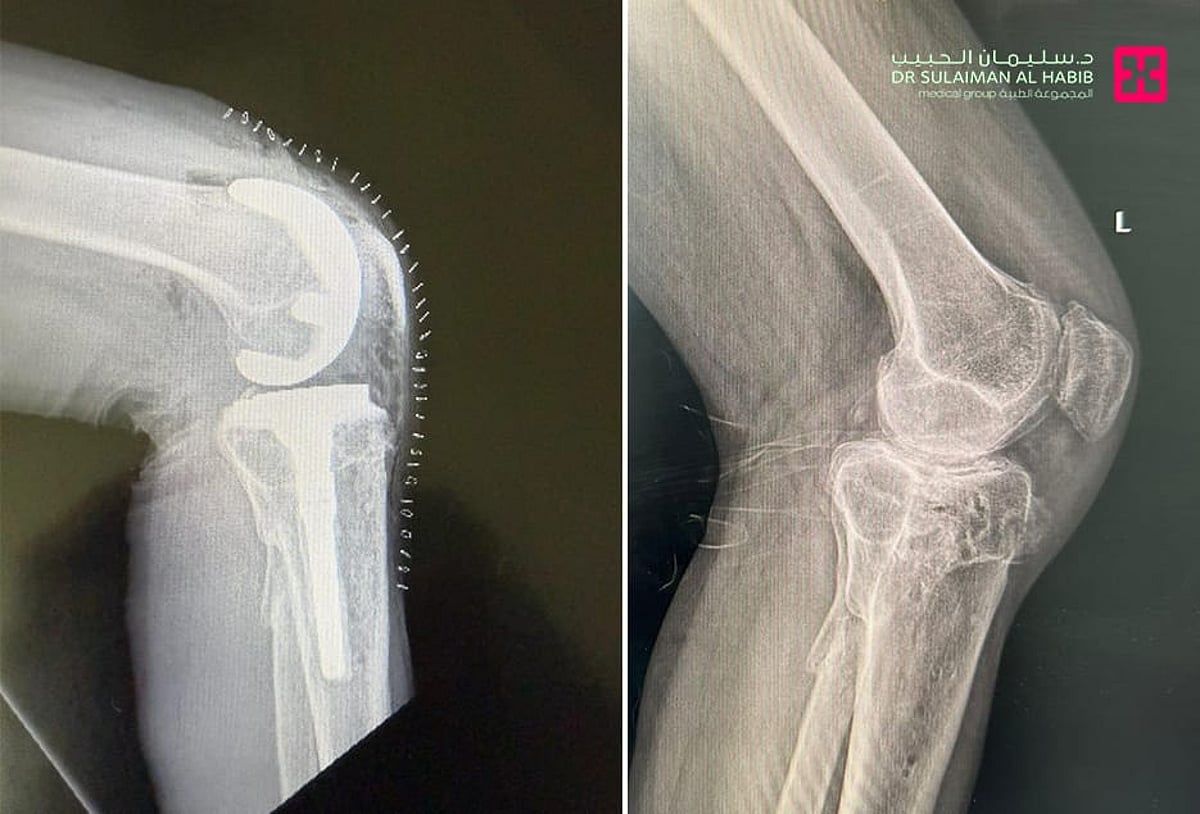

الذي قال أن المراجع وهو في العقد الخامس من العمر، جاء إلى المستشفى بسبب معاناته من خشونة متقدمة في مفصل الركبة اليسرى، نتيجة كسر قديم تم تثبيته بعملية رد مفتوح وتثبيت داخليORIF منذ سنوات طويلة. مضيفاً أنه خضع لفحوصات دقيقة أظهرت تغيّرات وخشونة بعد الكسر، مع تضيق في المسافة المفصلية وتصلب عظمي، وأجريت له عملية متقدمة تم فيها استبدال كلي للركبة باستخدام مفصل صناعي مزود بدعامة للساق، مطبوع بالتقنية ثلاثية الأبعاد بمساعدة الأشعة المقطعية، وجرت العملية تحت التخدير النصفي، انتهت ولله الحمد بالنجاح التام.

وأظهر المراجع تحسنًا واضحًا بعد العملية، إذ بدأ التحرك على قدميه باستخدام المشاية، والعلاج الطبيعي بعد ساعات من العملية، وفي خلال أيام قليلة وصل مدى الحركة من 0-120 درجة.

واستطرد أ. د. الجاسر قائلاً أن خشونة المفصل الناتجة عن الكسر تُعد من التحديات الجراحية الصعبة، حيث تصاحبها التشوهات وفقدان العظام والتغير في شكل المفصل الطبيعي. وغالباً ما تتطلب عمليات الاستبدال الكلي للركبة التقليدية تعديلات كبيرة أثناء الجراحة، لتحقيق المحاذاة الدقيقة، في حين أن تقنية الطباعة ثلاثية الأبعاد، تتميز بدقة أعلى في التطابق والمحاذاة، وتقليل زمن العملية الجراحية، وكذلك كمية العظم المزال أثناء الجراحة، إضافة إلى تسريع الشفاء وتحسن النتائج الوظيفية.

وختم أ. د. الجاسر حديثه بالتأكيد على أن هذه الحالة تُبرز أهمية وفوائد الاستبدال الكلي للركبة بهذه التقنية في الحالات المعقدة، التي تتضمن تشوهات وتشريحاً غير طبيعي نتيجة الكسور القديمة، ففي الوقت الذي قد تواجه المفاصل الجاهزة التقليدية صعوبة في التكيف مع هذه التغيرات، فإن المفصل المطبوع بناءً على بيانات التصوير المقطعي، يقدم ملاءمة تشريحية مثالية، وتحكماً أدق في ميكانيكية المفصل، لذلك فإن الطباعة ثلاثية الأبعاد تمثل بالفعل عصرًا جديداً في جراحات المفاصل الصناعية بفضل إمكانياتها في تخصيص الحلول لكل مراجع على حدة.